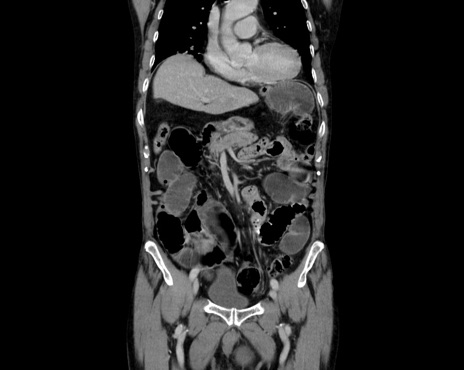

症例26(冠状断像)

【症例】80歳代男性

【主訴】嘔吐

【現病歴】昨晩2回嘔吐あり、今朝になっても嘔吐あり。来院。

【既往歴】胃潰瘍

【身体所見】意識清明、BT 37.6℃、BP 166/95mmHg、HR 100bpm、SpO2 97%、腹部:平坦・軟、腸蠕動音聴取良好、圧痛なし。

【データ】WBC 21900、CRP 1.4